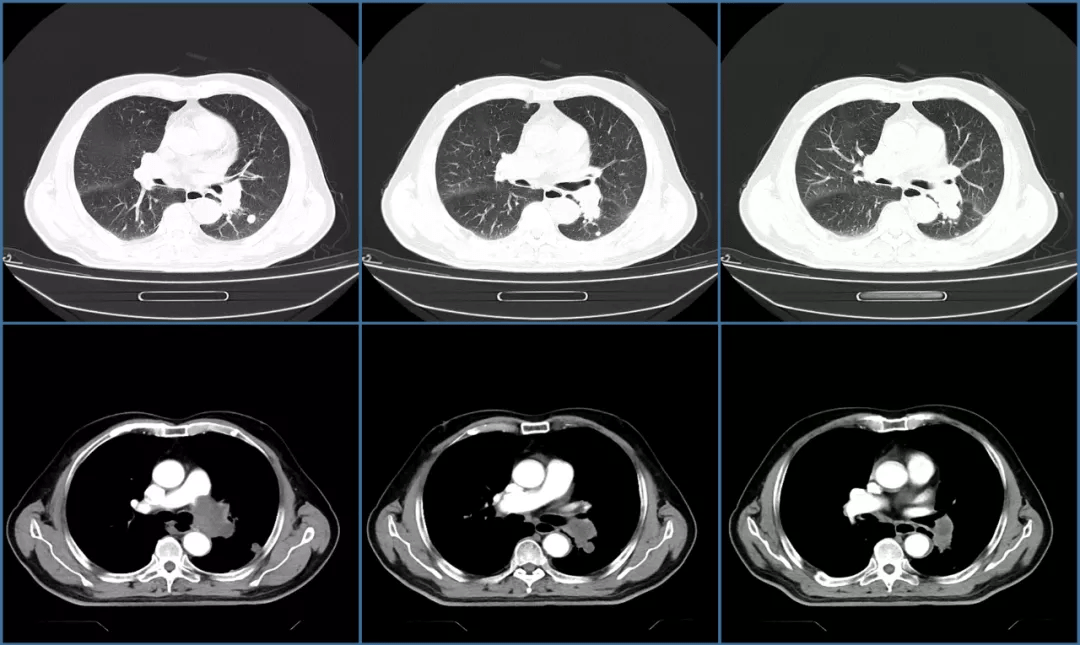

这样的充盈缺损是肺栓塞

图片尺寸1080x702

图片尺寸1080x645